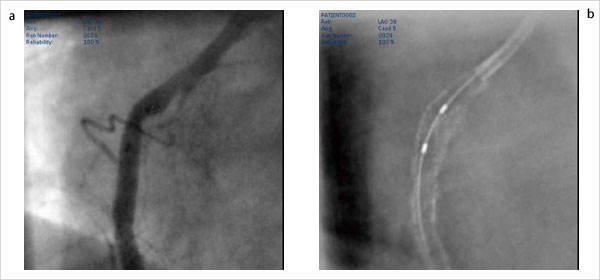

簡単な撮影だけで瞬時に視認性の低いステントを強調するStentBoostは,ステント拡張後の評価,再拡張時のバルーンの位置決めなど多くの場面で活用され,高い評価を得ている(図1)。しかしながら,デバイスのみの強調であるため,実際に術者が必要とする血管壁との相関関係を把握するには不十分であった。この要望に対応するため,従来の撮影に,わずかな造影剤注入フェーズを加えることで,血管壁を強調表現し比較できるアプリケーションが“StentBoost Subtract”である(図2)。

この機能により,ステント留置時の位置確認,ステント拡張後の状態,再拡張時のバルーンの位置決めなど,従来に比べ大幅に機能が拡張された。このアプリケーションの特長は,ダブルマーカーさえ留置された状態であれば,簡単な撮影とわずかな造影だけで容易に,かつ低コストで使えることである。視認性が低くなる傾向にある薬剤溶出性ステント(DES)などにも対応でき,より正確なPCIをサポートするツールとしてさらに改良を重ねられている。

図1 3D-CA(a)とStentBoost(b)

図2 StentBoost Subtract

血管のブースト画像(a)とStentBoost画像(b)が,交互にムービ表示に切り替わり,血管壁とステント(病変部)の位置関係を把握できる。